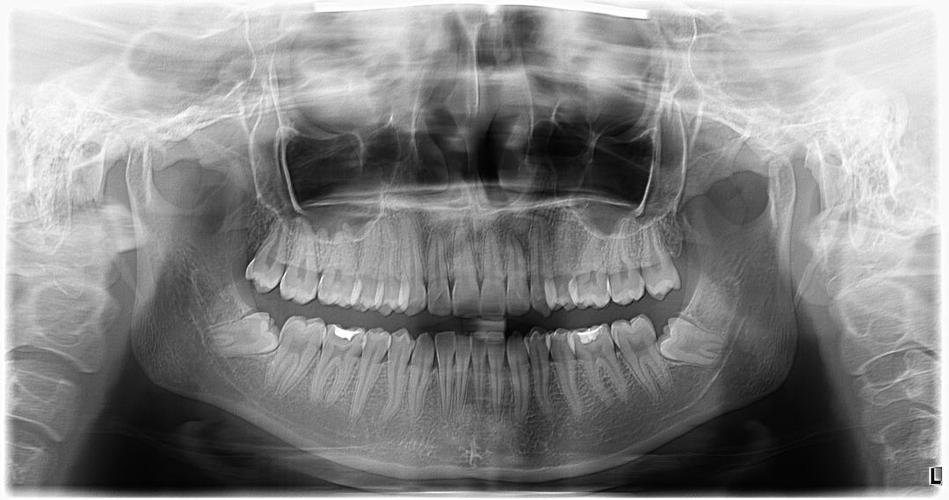

智齿有神经吗,拔智齿疼吗

哭哭,我的智齿太靠近神经管了怎么办

智齿紧贴神经该怎么办上篇

下颌智齿离下牙槽神经管越近,难度也越大.

拔智齿伤神经吗?

阻生智齿该不该拔